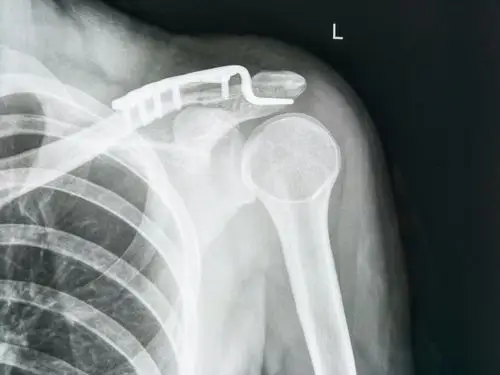

x线显示锁骨远端骨折

锁骨远端骨折

锁骨远端骨折肩锁关节在位选择钩钢板还是锁骨远端钢板

锁骨远端骨折经典术式

肩锁关节脱位锁骨远端骨折关节镜下微型钢板固定喙锁 斜方韧带重建术